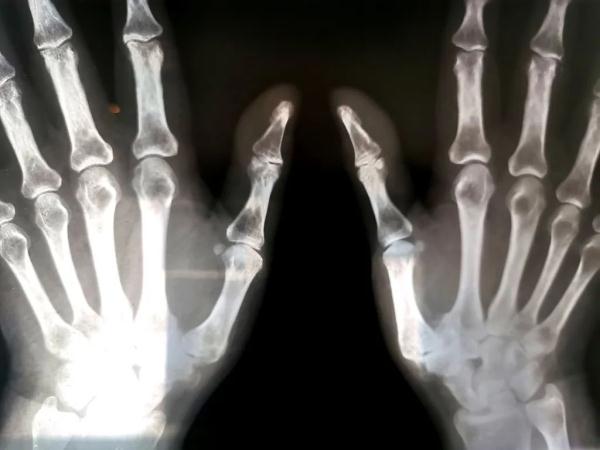

接诊后医生发现,黄先生的左手骨头上长了一颗内生性软骨瘤,把正常的骨头都‘融’成‘豆腐渣’了,所以骨头才会一碰就裂开,需要刮除肿瘤组织同时固定骨折的掌骨。

专家提醒,软骨瘤千万不能小瞧,任其发展的话,可出现大小不一的溶骨性病灶,会破坏骨质,导致骨头空洞,影响关节活动,最终会导致手指或者脚趾丧失活动功能。

1.40%-65%的单发内生软骨瘤好发于手部,然后是双足,也可累及肱骨、股骨和胫骨。发生于脊椎突向椎管内可引起截瘫。

2.关节周围肿块常为首发症状,一般无症状。肿瘤较大者压迫附近的肌腱、血管和神经时出现疼痛。当出现疼痛加剧就要警惕病理性骨折以及肿瘤恶变的风险。